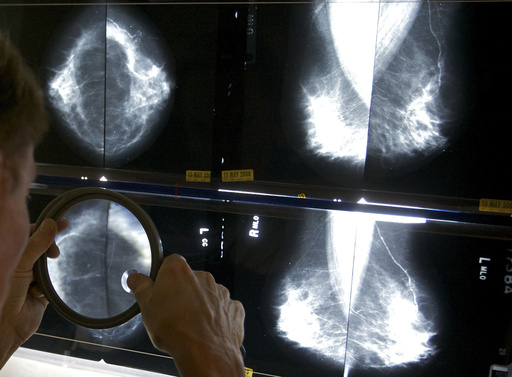

Regular mammograms to screen for breast cancer should start younger, at age 40, according to an influential U.S. task force. Women ages 40 to 74 should get screened every other year, the group said.

Previously, the task force had said women could choose to start breast cancer screening as young as 40, with a stronger recommendation that they get the exams every two years from age 50 through 74.

The announcement Tuesday from the U.S. Preventive Services Task Force makes official a draft recommendation announced last year. The recommendations were published in the Journal of the American Medical Association.

Age 40 is when mammograms should start for women, transgender men and nonbinary people at average risk. They should have the X-ray exam every other year, according to the new guidance. Other groups recommend annual mammograms, starting at 40 or 45.